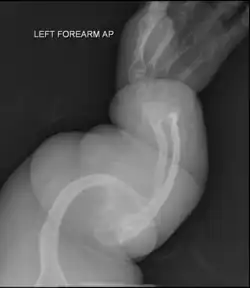

- Type V – Having the same clinical features as type IV, it can be clinically distinguished by observing a "mesh-like" appearance to a bone biopsy under a microscope. Type V can be further distinguished from other types of OI by the "V triad": an opaque band (visible on X-ray) adjacent to the growth plates; hypertrophic calluses (abnormally large masses of bony repair tissue) which form at fracture sites during the healing process; and calcification of the interosseous membrane of the forearm,[50] which may make it difficult to turn the wrist.[1]: 429 Other features of this condition may include pulled elbow, and, as in other types of OI, long bone bowing and hearing loss.[64] Cases of this type are caused by mutations in the IFITM5 gene on chromosome 11p15.5.[64][49] The separation of type V from type IV OI, its clinical type, was initially suggested even before its genetic cause was known, by Glorieux et al. in 2000.[50][65] Type V is relatively common compared to other genetically defined types of OI—4% of OI patients at the genetics department of the Brazilian Hospital de Clínicas de Porto Alegre were found to have it.[66]